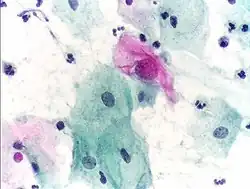

Squamous metaplasia of the cervix, with typical features. Pap stain.

Pap tests commonly examine epithelial abnormalities, such as metaplasia, dysplasia, or borderline changes, all of which may be indicative of CIN. Nuclei will stain dark blue, squamous cells will stain green and keratinised cells will stain pink/ orange. Koilocytes may be observed where there is some dyskaryosis (of epithelium). The nucleus in koilocytes is typically irregular, indicating possible cause for concern; requiring further confirmatory screens and tests.